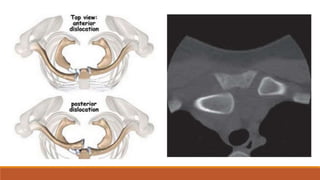

Posterior dislocation of Sternoclavicular joint

Injury to Trachea/Oesophagus/Great Vessels/Superior Mediastinum

MISCELLANOUS Posterior dislocation ofSternoclavicular joint Injury to Trachea/Oesophagus/Great Vessels/Superior Mediastinum